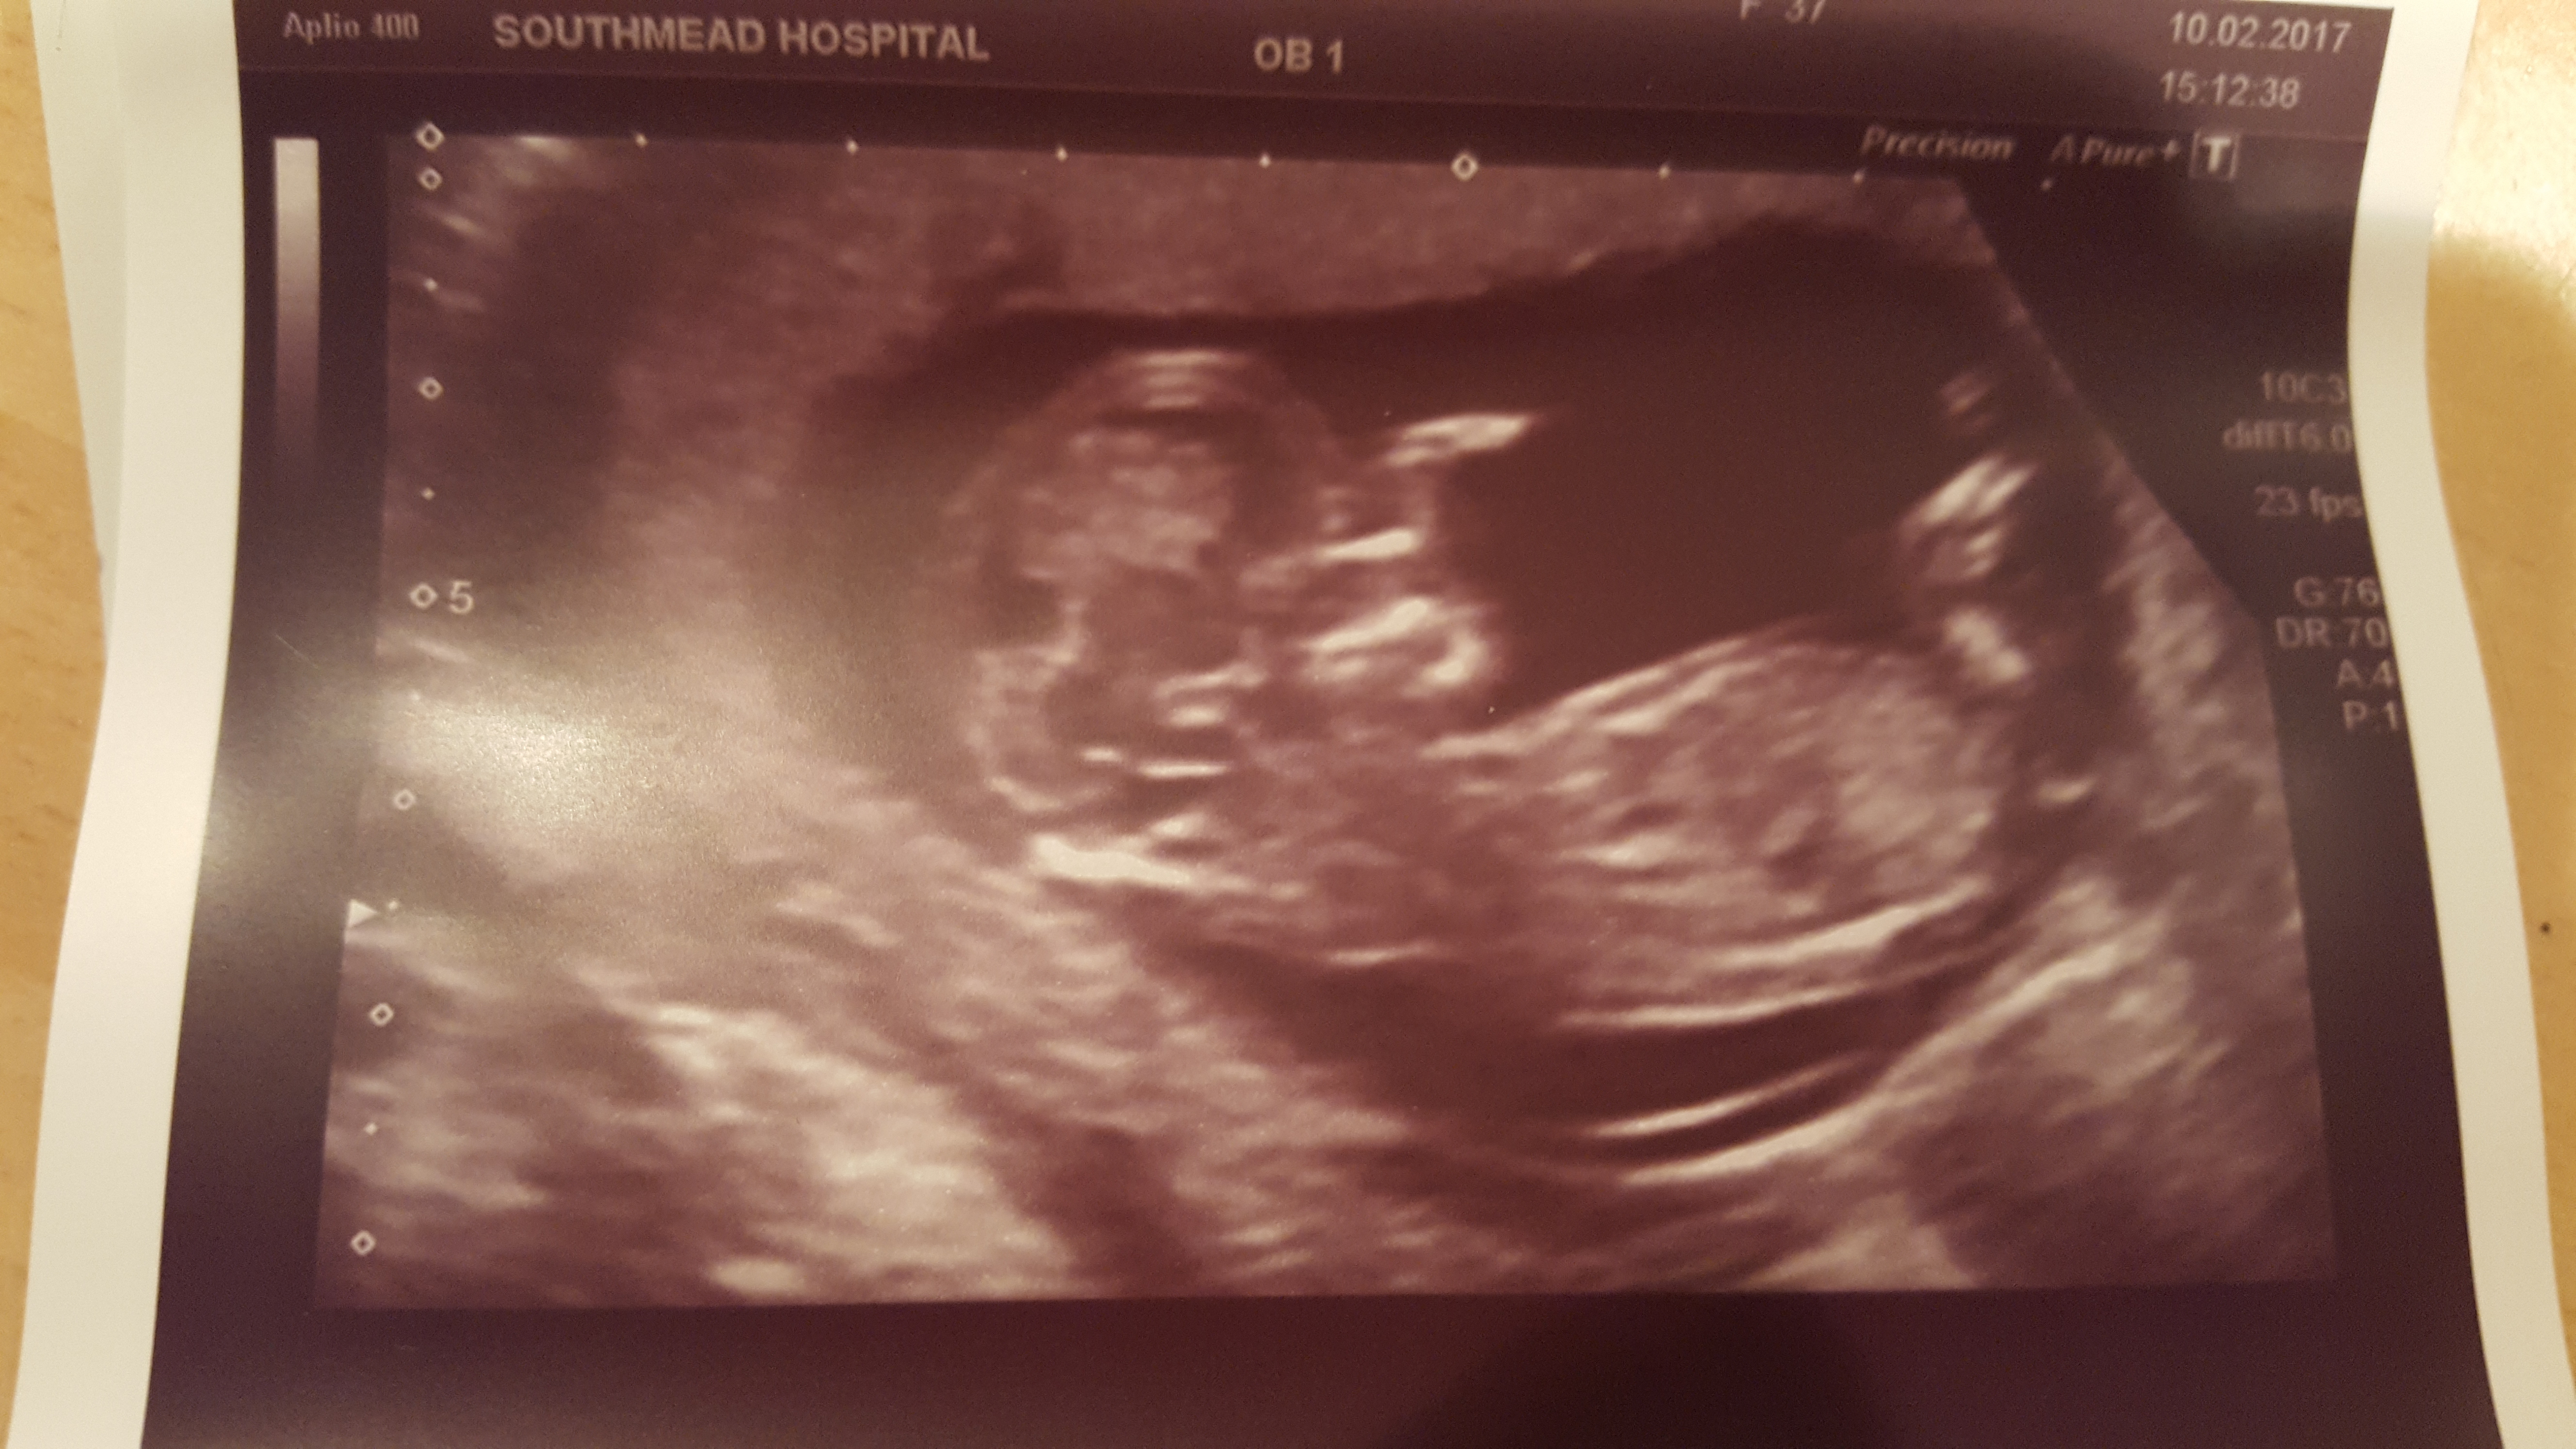

Hi everyone, just wanted to update as promised.......

Im having my 4th SON!!

Thankyou all for your guesses.x

Congratulations on your little boy. I'm also happy to have any of your blue dust rub off on me.

Congrats with your wonderful little boy!!! :DS::fami03:

Enjoy every second of him :)